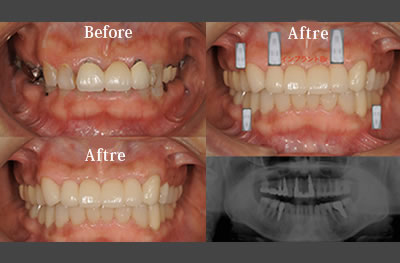

術前/術後